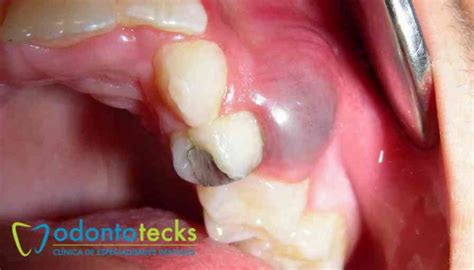

Si de repente detectas que tu encía se inflama en determinada zona, y que comienza a formarse una pequeña fístula por encima del diente, podemos estar hablando de un quiste dental o odontogénico. Este se caracteriza además por ser semiblando y escamoso al tacto.

- Dentígero: Este quiste se produce alrededor de dientes no erupcionados como muelas del juicio que aún no han salido y provoca la pérdida ósea a su alrededor.